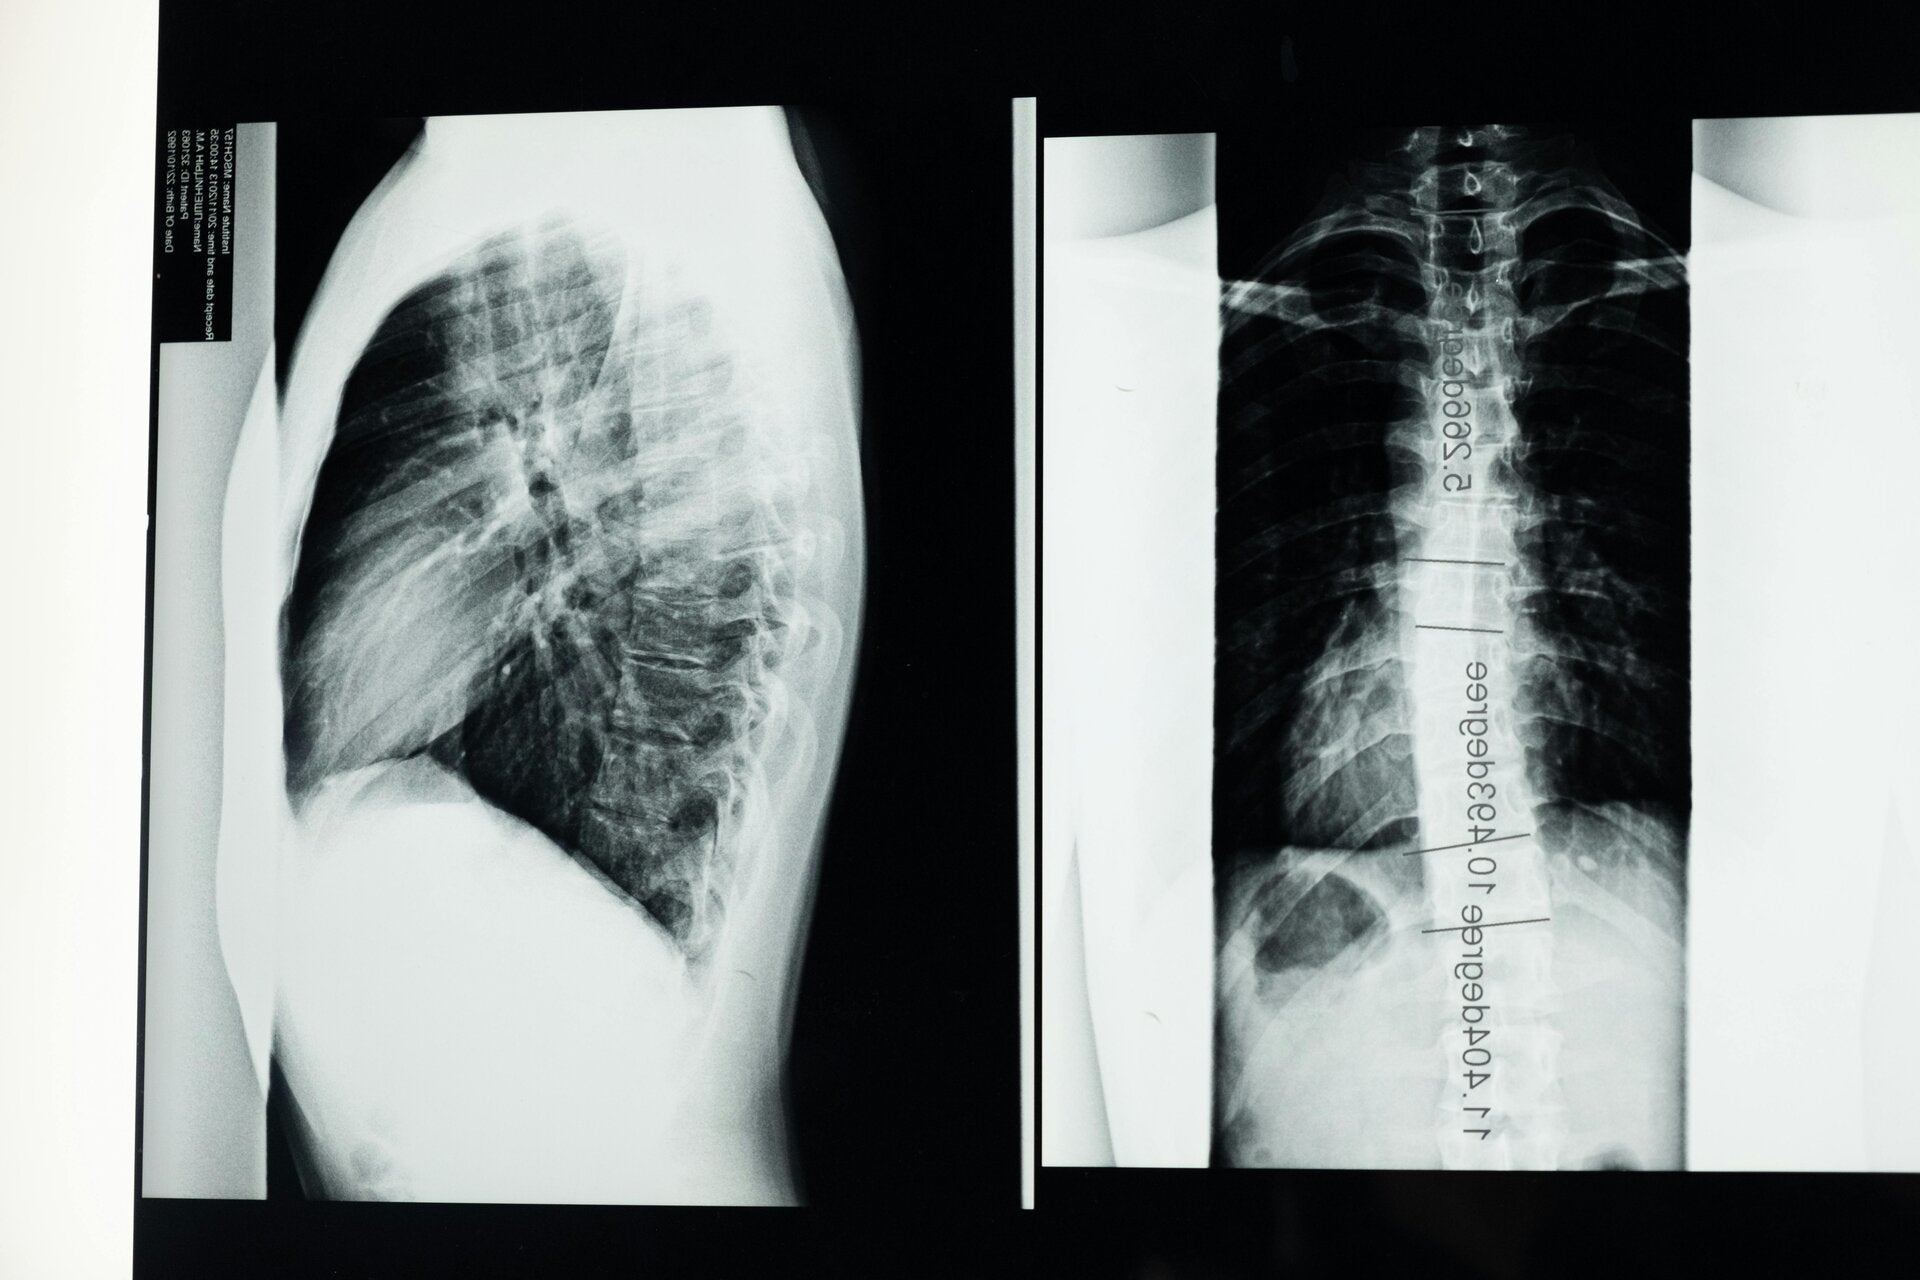

• Luchtwegaandoeningen: bij aandoeningen zoals COPD raakt het diafragma afgeplat en verliest het spierkracht.